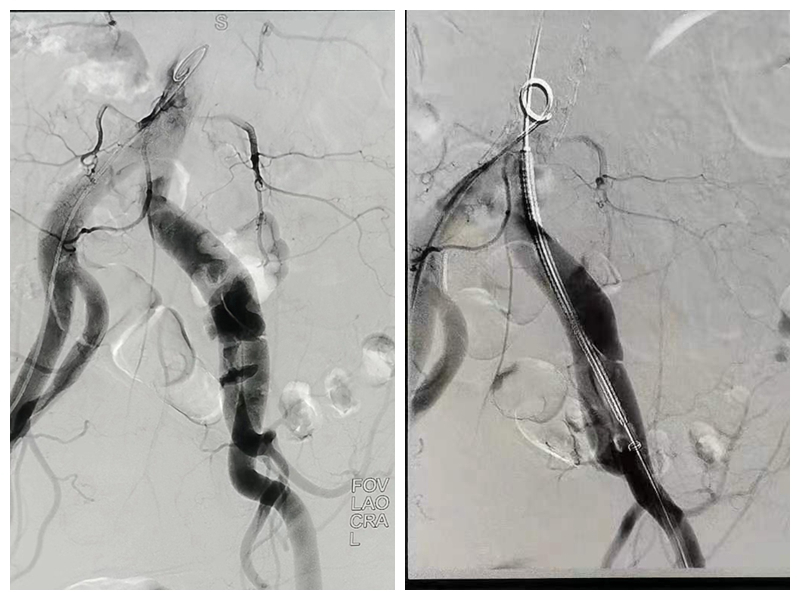

病情诊断终于出现了转机,腹部血管造影显示:腹部动脉粥样硬化,左侧髂总动脉及髂外动脉起始处夹层,且假腔宽约9.64mm。“嘱患者卧床,监护,控制血压,马上联系心内和介入科会诊”, 心内科睢勇副主任医师、外科李俊峰副主任医师等在接到通知后很快到位。 “假腔较大,血管极有可能会被撕裂,幸好发现的早,得马上安排手术”,介入科刘主任说。经过1个多小时的紧张手术,手术团队成功将患者危情解除,手术顺利结束,目前患者进入术后康复阶段。